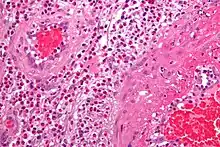

- The definite diagnosis of vasculitis is established after a biopsy of involved organ or tissue, such as skin, sinuses, lung, nerve, brain, and kidney. The biopsy elucidates the pattern of blood vessel inflammation.

- Some types of vasculitis display leukocytoclasis, which is vascular damage caused by nuclear debris from infiltrating neutrophils.[15] It typically presents as palpable purpura.[15] Conditions with leucocytoclasis mainly include hypersensitivity vasculitis (also called leukocytoclastic vasculitis) and cutaneous small-vessel vasculitis (also called cutaneous leukocytoclastic angiitis).